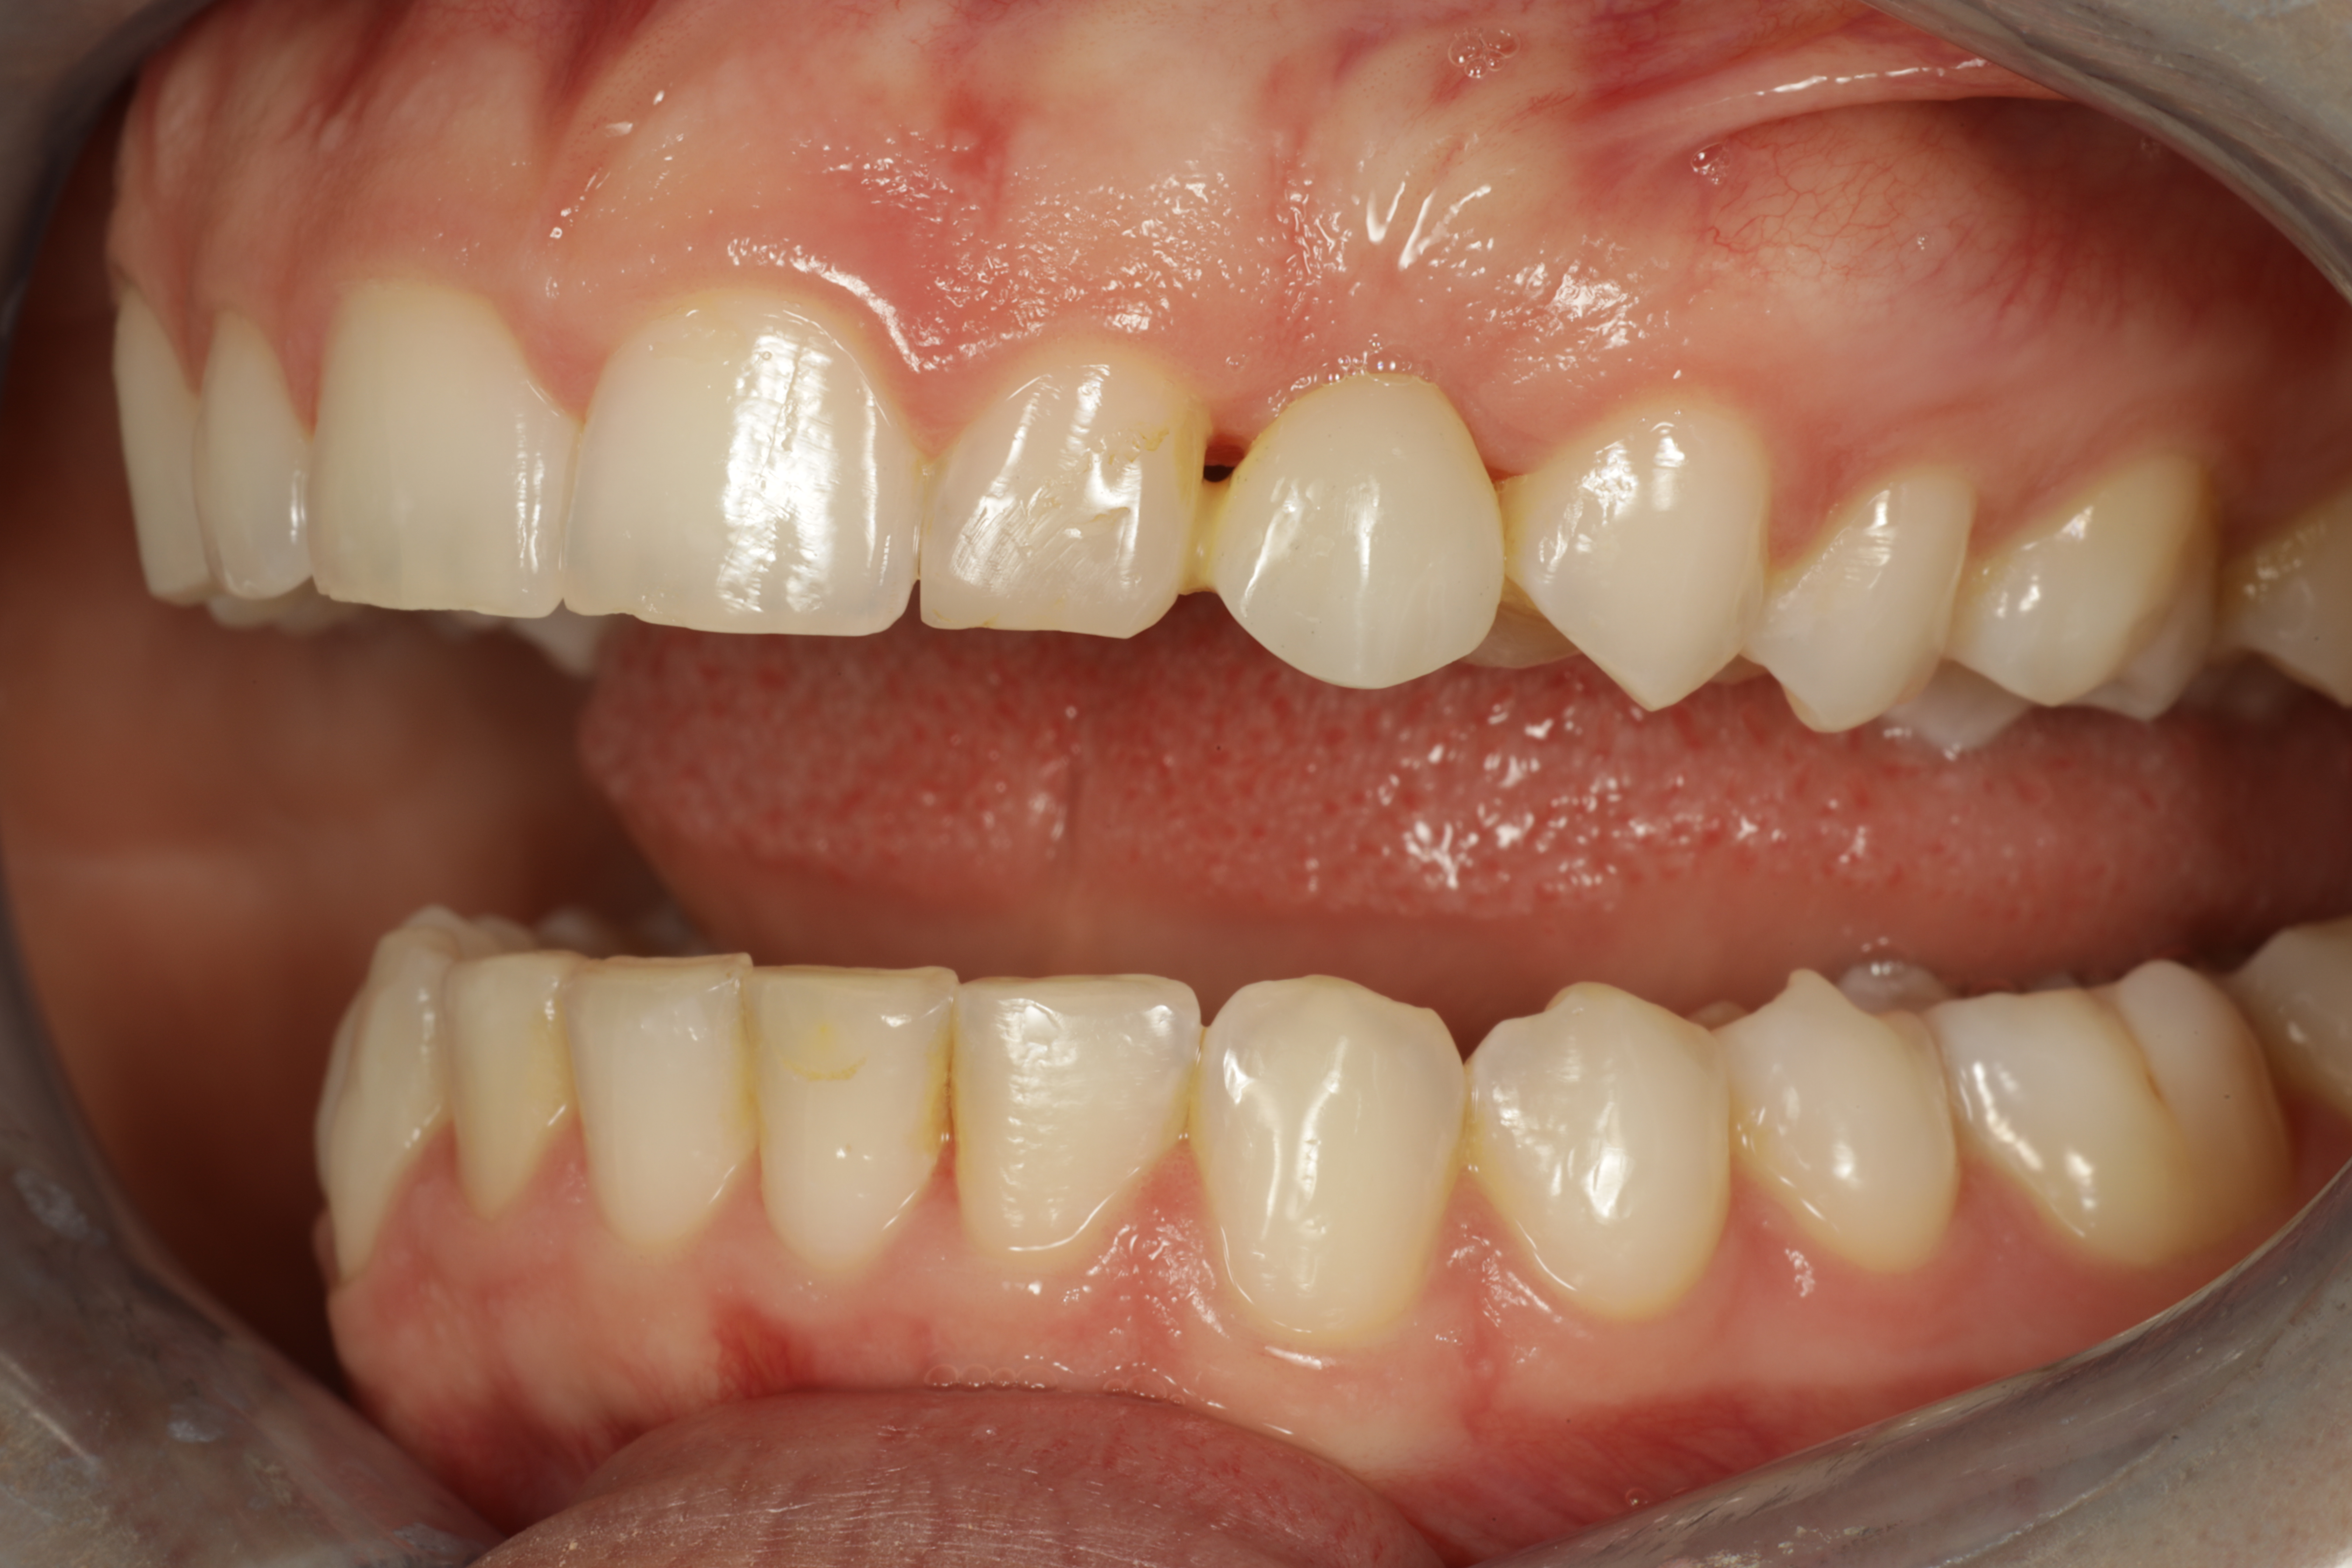

Synnynnäisesti puuttuva kulmahammas. Alkukuvissa hammas on korvattu muovisella kevytsillalla. Silta purettu pois ja asetettu implantti puuttuvan hampaan tilalle. Kirurgina Jarno Savolainen eSmile Helsinki. Hammasteknikkomestari Aki Lindén.

Alkutilanne ennen kevytsiltaa. Kulmahammas poikittain syvällä luun sisällä, maitohammas pysyvän kulmahampaan paikalla. Hoidon aikana molemmat poistettu. Ja implantti asetettu paikoilleen